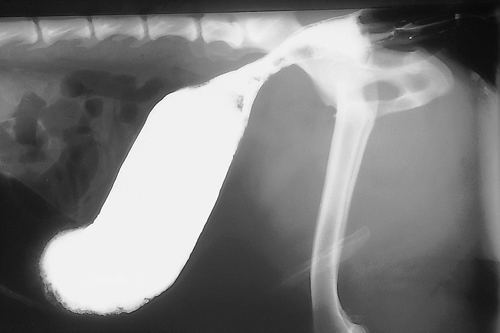

Image from 'Small Animal Abdominal and Metabolic Disorders', with permission from Manson Publishing, as part of the OVAL. This is a radiograph of a dog after a barium enema showing megacolon. |